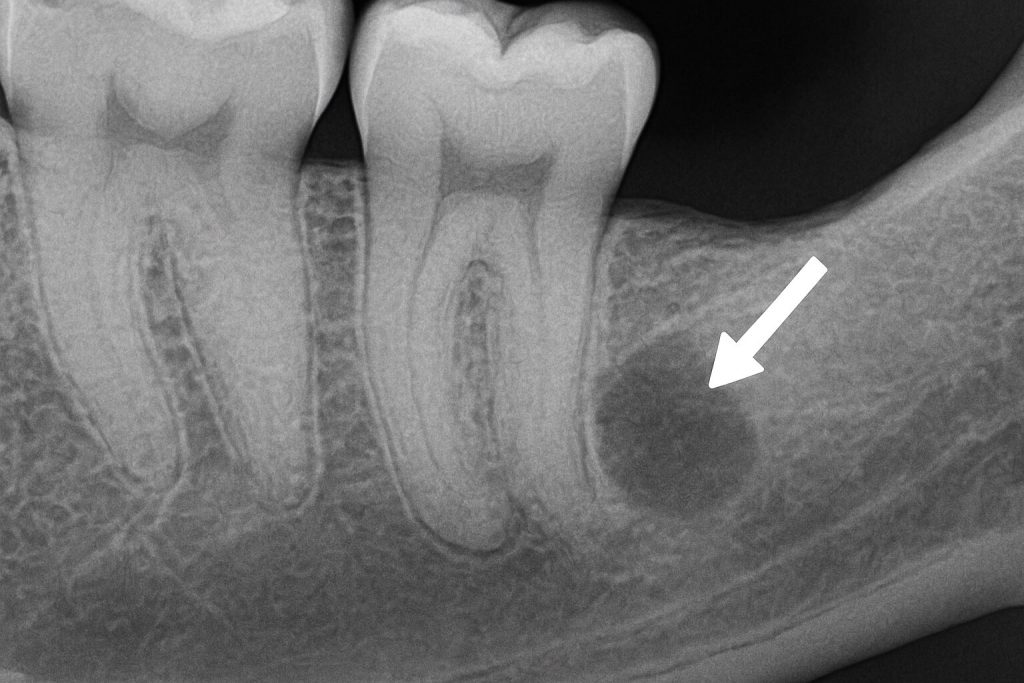

2. خراج تحت الضرس

يظهر أسفل جذر الضرس وقد لا يُرى بالعين المجردة، ويُكتشف غالبًا باستخدام الأشعة السينية.

هذا النوع من الخراج يكون مزمنًا في بعض الحالات، ويُسبب ألمًا عند العض أو عند الضغط على الضرس.

معلومة هامة: قد يكون السبب هو معالجة قناة الجذر بشكل غير مكتمل.

صورة خراج الأسنان تحت الضرس يظهر في الأشعة السينية، يتمركز أسفل الجذر ويسبب ألمًا عند الضغط أو العض، وقد يكون ناتجًا عن علاج غير مكتمل.